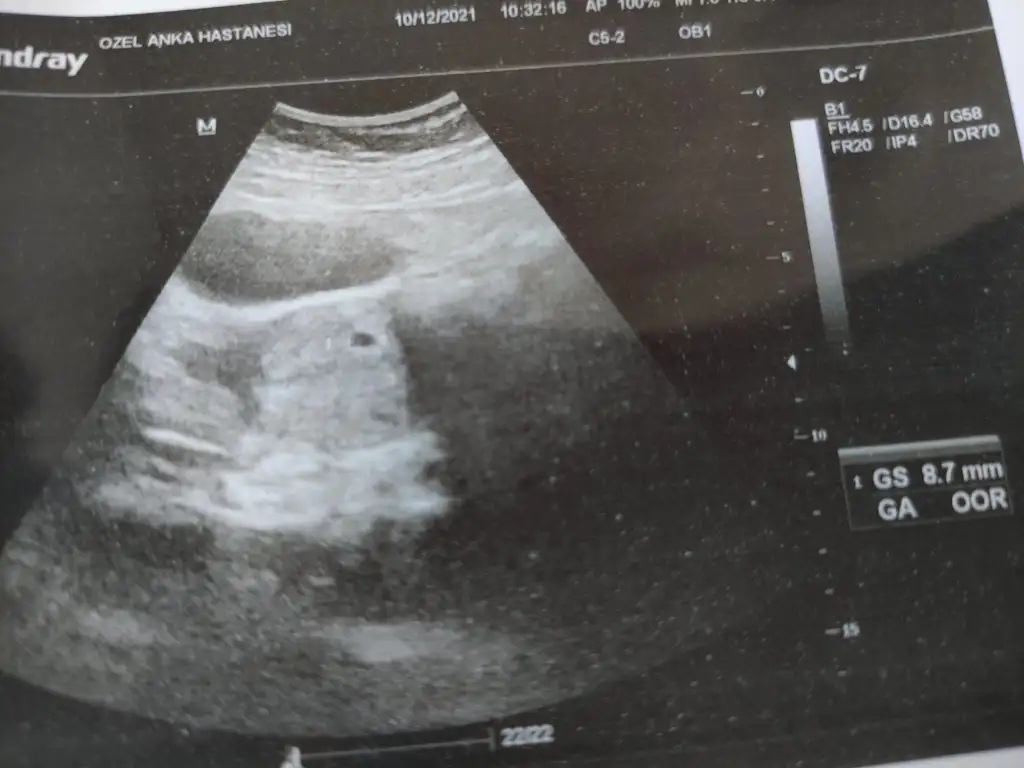

Kızlar doktordan çıktım şimdi 5+4 üm karından görünmedi vajinal gördü ama keseyi gördü sadece 10 mm dedi yolksac ı sordum görüntü net değil göremedim 10 gün sonra tekrar gel dedi. Ekrana baktım kesenin kenarında yüzük gibi bişey var ama belli belirsiz 😳 oof of şimdi nasıl geçecek 10 gün boş gebelik mi diye kendimi yiyip durcam 🥺🥺

Bende bugün gittim kese görüldü ama karından baktı.beta 6133 geldi . Bana da 10 gün sonra gel bakalım dedi